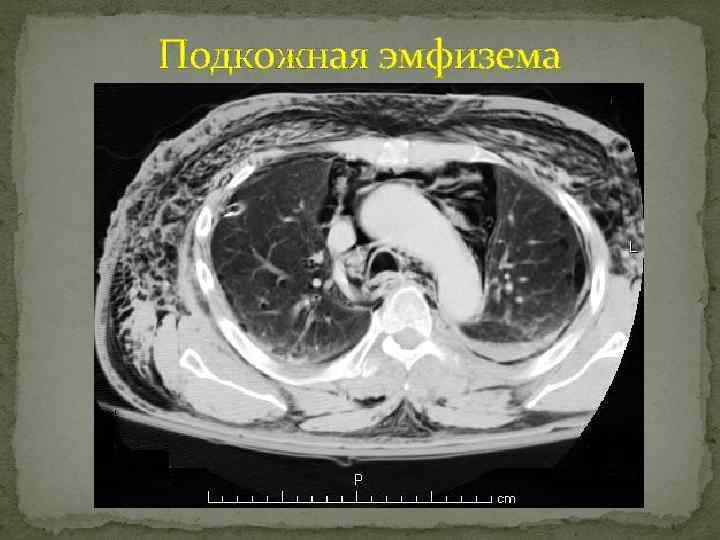

Подкожная эмфизема